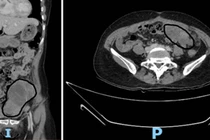

Bé gái 15 tuổi ở Hà Nội mắc u nhầy buồng trứng hiếm gặp